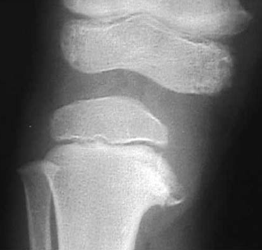

défaut de croissance du tibia interne supérieur: bilatérale 60%

- Lesion métaphysaire tibiale interne

-Angle entre physe et la diaphyse

Déformation en varus: jambes arquées de longueur différente

proéminence médiane du tibia proximal